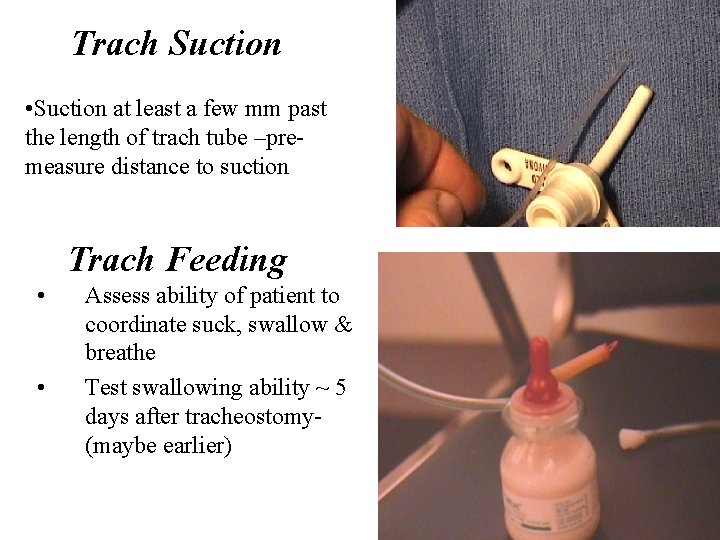

Trach Suction • Suction at least a few mm past the length of trach tube –premeasure distance to suction Trach Feeding • • Assess ability of patient to coordinate suck, swallow & breathe Test swallowing ability ~ 5 days after tracheostomy- (maybe earlier)